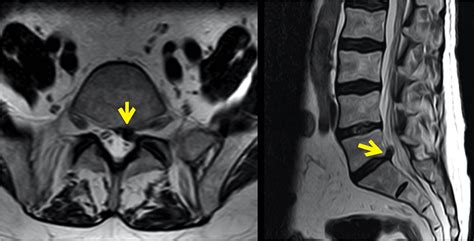

Medical Conditions